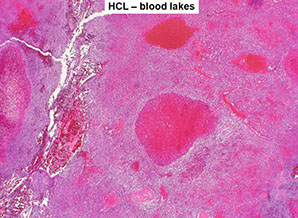

Tissue shows "fried egg" morphology, reticulin fibrosis, blood lakes, mast cells frequent

In spleen, see BLOOD LAKES

HCL gross - Diffuse red pulp enlargement, blood lakes

HCL blood lakes